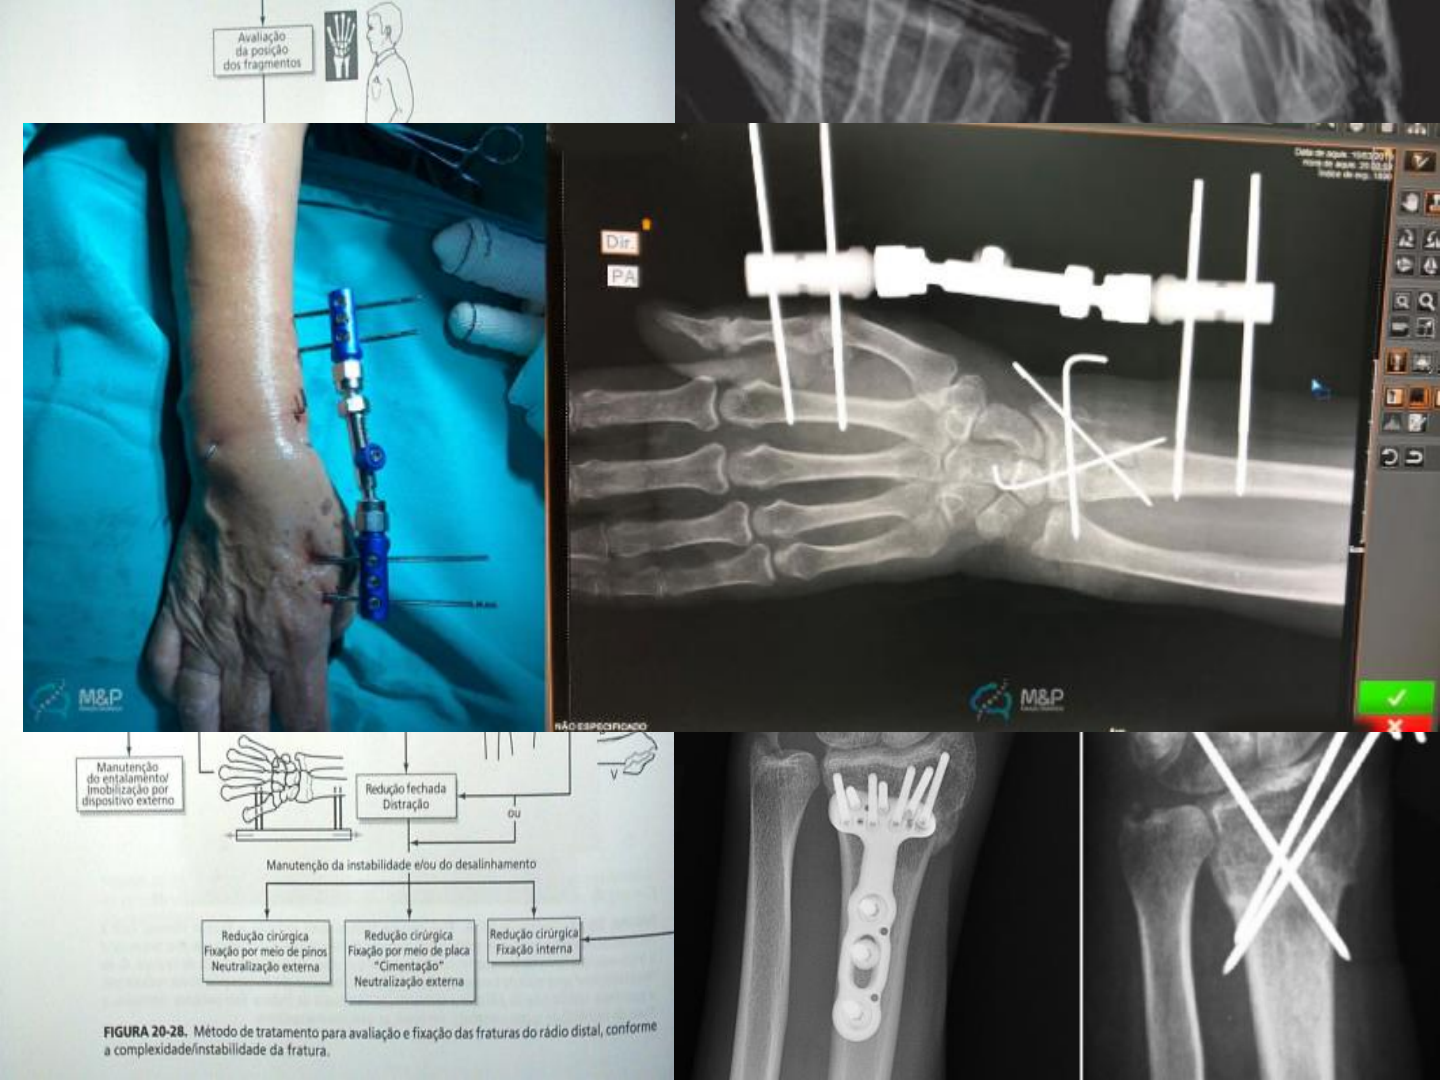

Fratura Rádio Distal Multifragmentar: Osteossíntese Volar para Estabilidade do Punho

O tratamento é feito com a imobilização gessada ou não gessada, placas e parafusos, percutanea ou fixação externa a depender do tipo e gravidade da fratura até que a fratura esteja estável